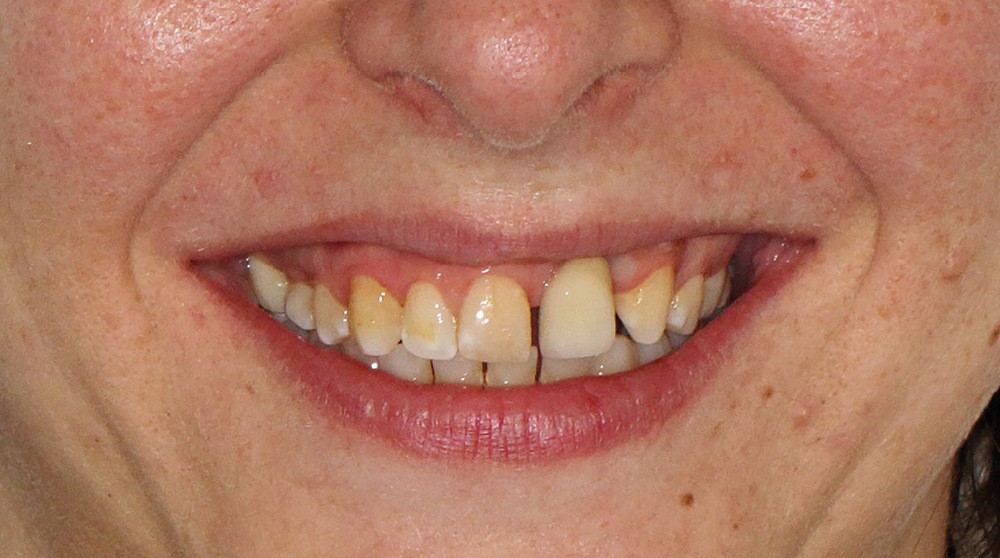

- au niveau esthétique : une couronne sur 21 disgracieuse et une déviation du milieu maxillaire vers la gauche (fig. 2) ;

- au niveau dentaire : une arcade maxillaire asymétrique avec déviation du milieu maxillaire à gauche. On note l’absence de 21, 22, 25, 35 et 45, une classe II droite et gauche avec infraclusion antérieure et la présence d’un implant en place de 21 avec un diastème de 3 mm entre 21 et 23 (fig. 3) ;